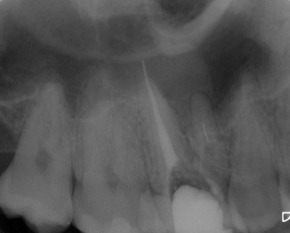

Nach Darstellung aller Wurzelkanaleingänge wird in einem zweiten Schritt das frakturierte Wurzelkanalinstrument dargestellt (Abb. 3 u. 4). Hierfür verwenden wir den Aufsatz 3E des Tigon+. Durch die schmale und lange Form des Instruments erreichen wir einen tiefen und schmalen Zugang.